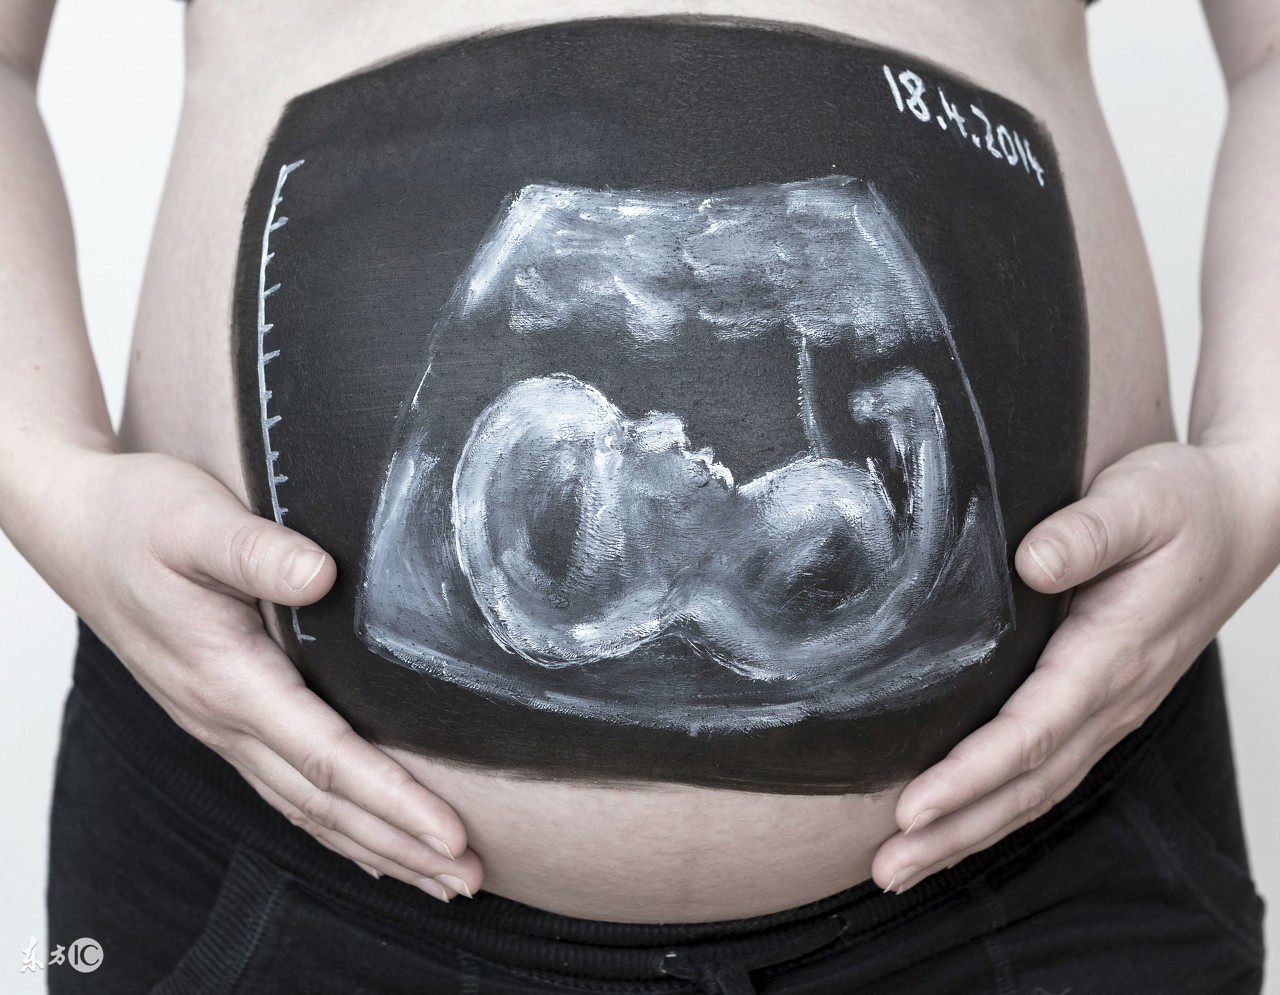

周力学介绍,这是目前国内外使用最广泛、最安全的胎儿影像学检查,可以观察胎儿大小、胎位、胎动、胎盘及羊水情况;还可以进行胎儿畸形筛查和血流动力学检测。随着科技的发展,当宝宝还未出世的时候,妈妈就可以通过三维和四维超声来观赏一下宝宝的小脸了。

完成了13+周产前III级彩超检查,又过了一个关卡的准妈妈们可以开始预约第三次产前超声(中孕产前III级彩超检查)了,也就是俗称的大排畸,也是很多准妈妈心心念念的三维检查。这项检查一般合适时机位于18周-24周。太小了宝宝还没发育好,检查价值不能完全达到,太晚了宝宝又比较大了,有的位置看得不太好,最佳时间一般位于21周-24周。这个阶段由于宝宝大部分器官已经发育,结构也比较清晰,可以进行的大部分器官结构筛查,可以排除大部分复杂胎儿畸形。